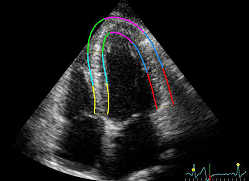

超音波検査

-

エコー図

虚血の例

- LAD虚血

- LCx虚血

- RCA虚血